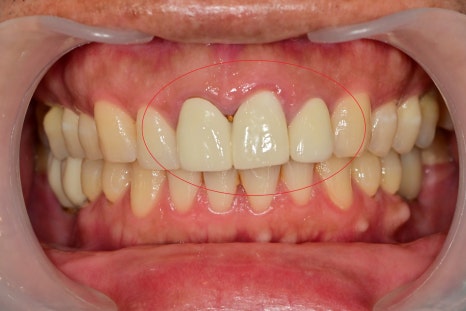

최종 심미보철물의 세팅 날입니다.

전과 비교해서 모양이나 색상이 자연스러워진 것을 볼 수 있습니다.

기존 치아의 색상이 약간 어두운 경우

미백을 추가적으로 하면 더 좋은 효과를 볼 수 있습니다.